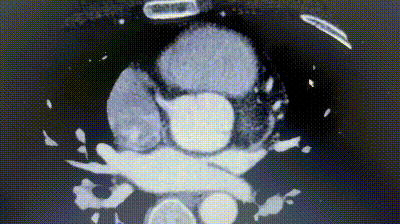

2. Coronary CTA revealed an anomalous origin of the left circumflex artery (LCX) from the right coronary sinus, with a course between the aorta and left atrium.

3. The distance between the ASD and the aberrant LCX was only about 6 mm.

Given the proximity of the defect to the coronary artery, a traditional metal occluder posed a risk of compression, especially during physical exertion. A biodegradable ASD occluder (BDASD-I 18 mm) was therefore selected for its flexibility, lower risk of long-term mechanical injury, and ability to degrade into carbon dioxide and water after completing the closure function.